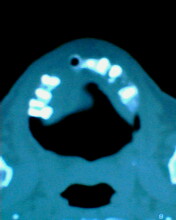

患者:男71岁,右侧上颚肿物无痛性生长7年.

右上颌骨近中线部见类圆形低密度区,上方见一液平,周围见一薄硬化环,前下方见一牙根,后方累及水平板。上方突入鼻腔前下部,下方突入口腔。

考虑:右侧上颌骨囊肿伴感染。